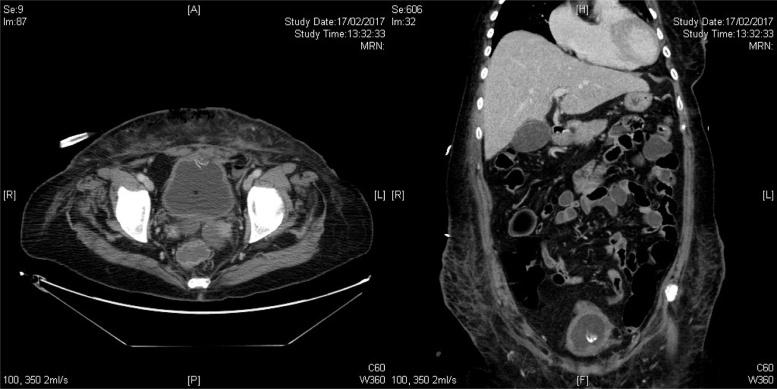

We hereby report a case of abdominal wall necrotizing fasciitis 21 months after laparoscopic incisional hernia repair in lower midline with dual mesh, due to mesh migration and erosion into urinary bladder, resulting in fistulation between bladder and abdominal wall. Repeated debridement and removal of mesh was required for sepsis control and the patient required intensive care support due to multi-organ failure. Subsequent repair of urinary bladder and abdominoplasty was performed after condition stabilized.

我们在此报告一例患者,在腹腔镜下经下腹正中切口使用双层补片修补切口疝21个月后,发生了腹壁坏死性筋膜炎,原因是补片移位并侵蚀膀胱,导致膀胱与腹壁之间形成瘘管。为控制脓毒症,需要反复清创并取出补片,由于多器官功能衰竭,患者需要重症监护支持。病情稳定后,随后进行了膀胱修复和腹壁成形术。